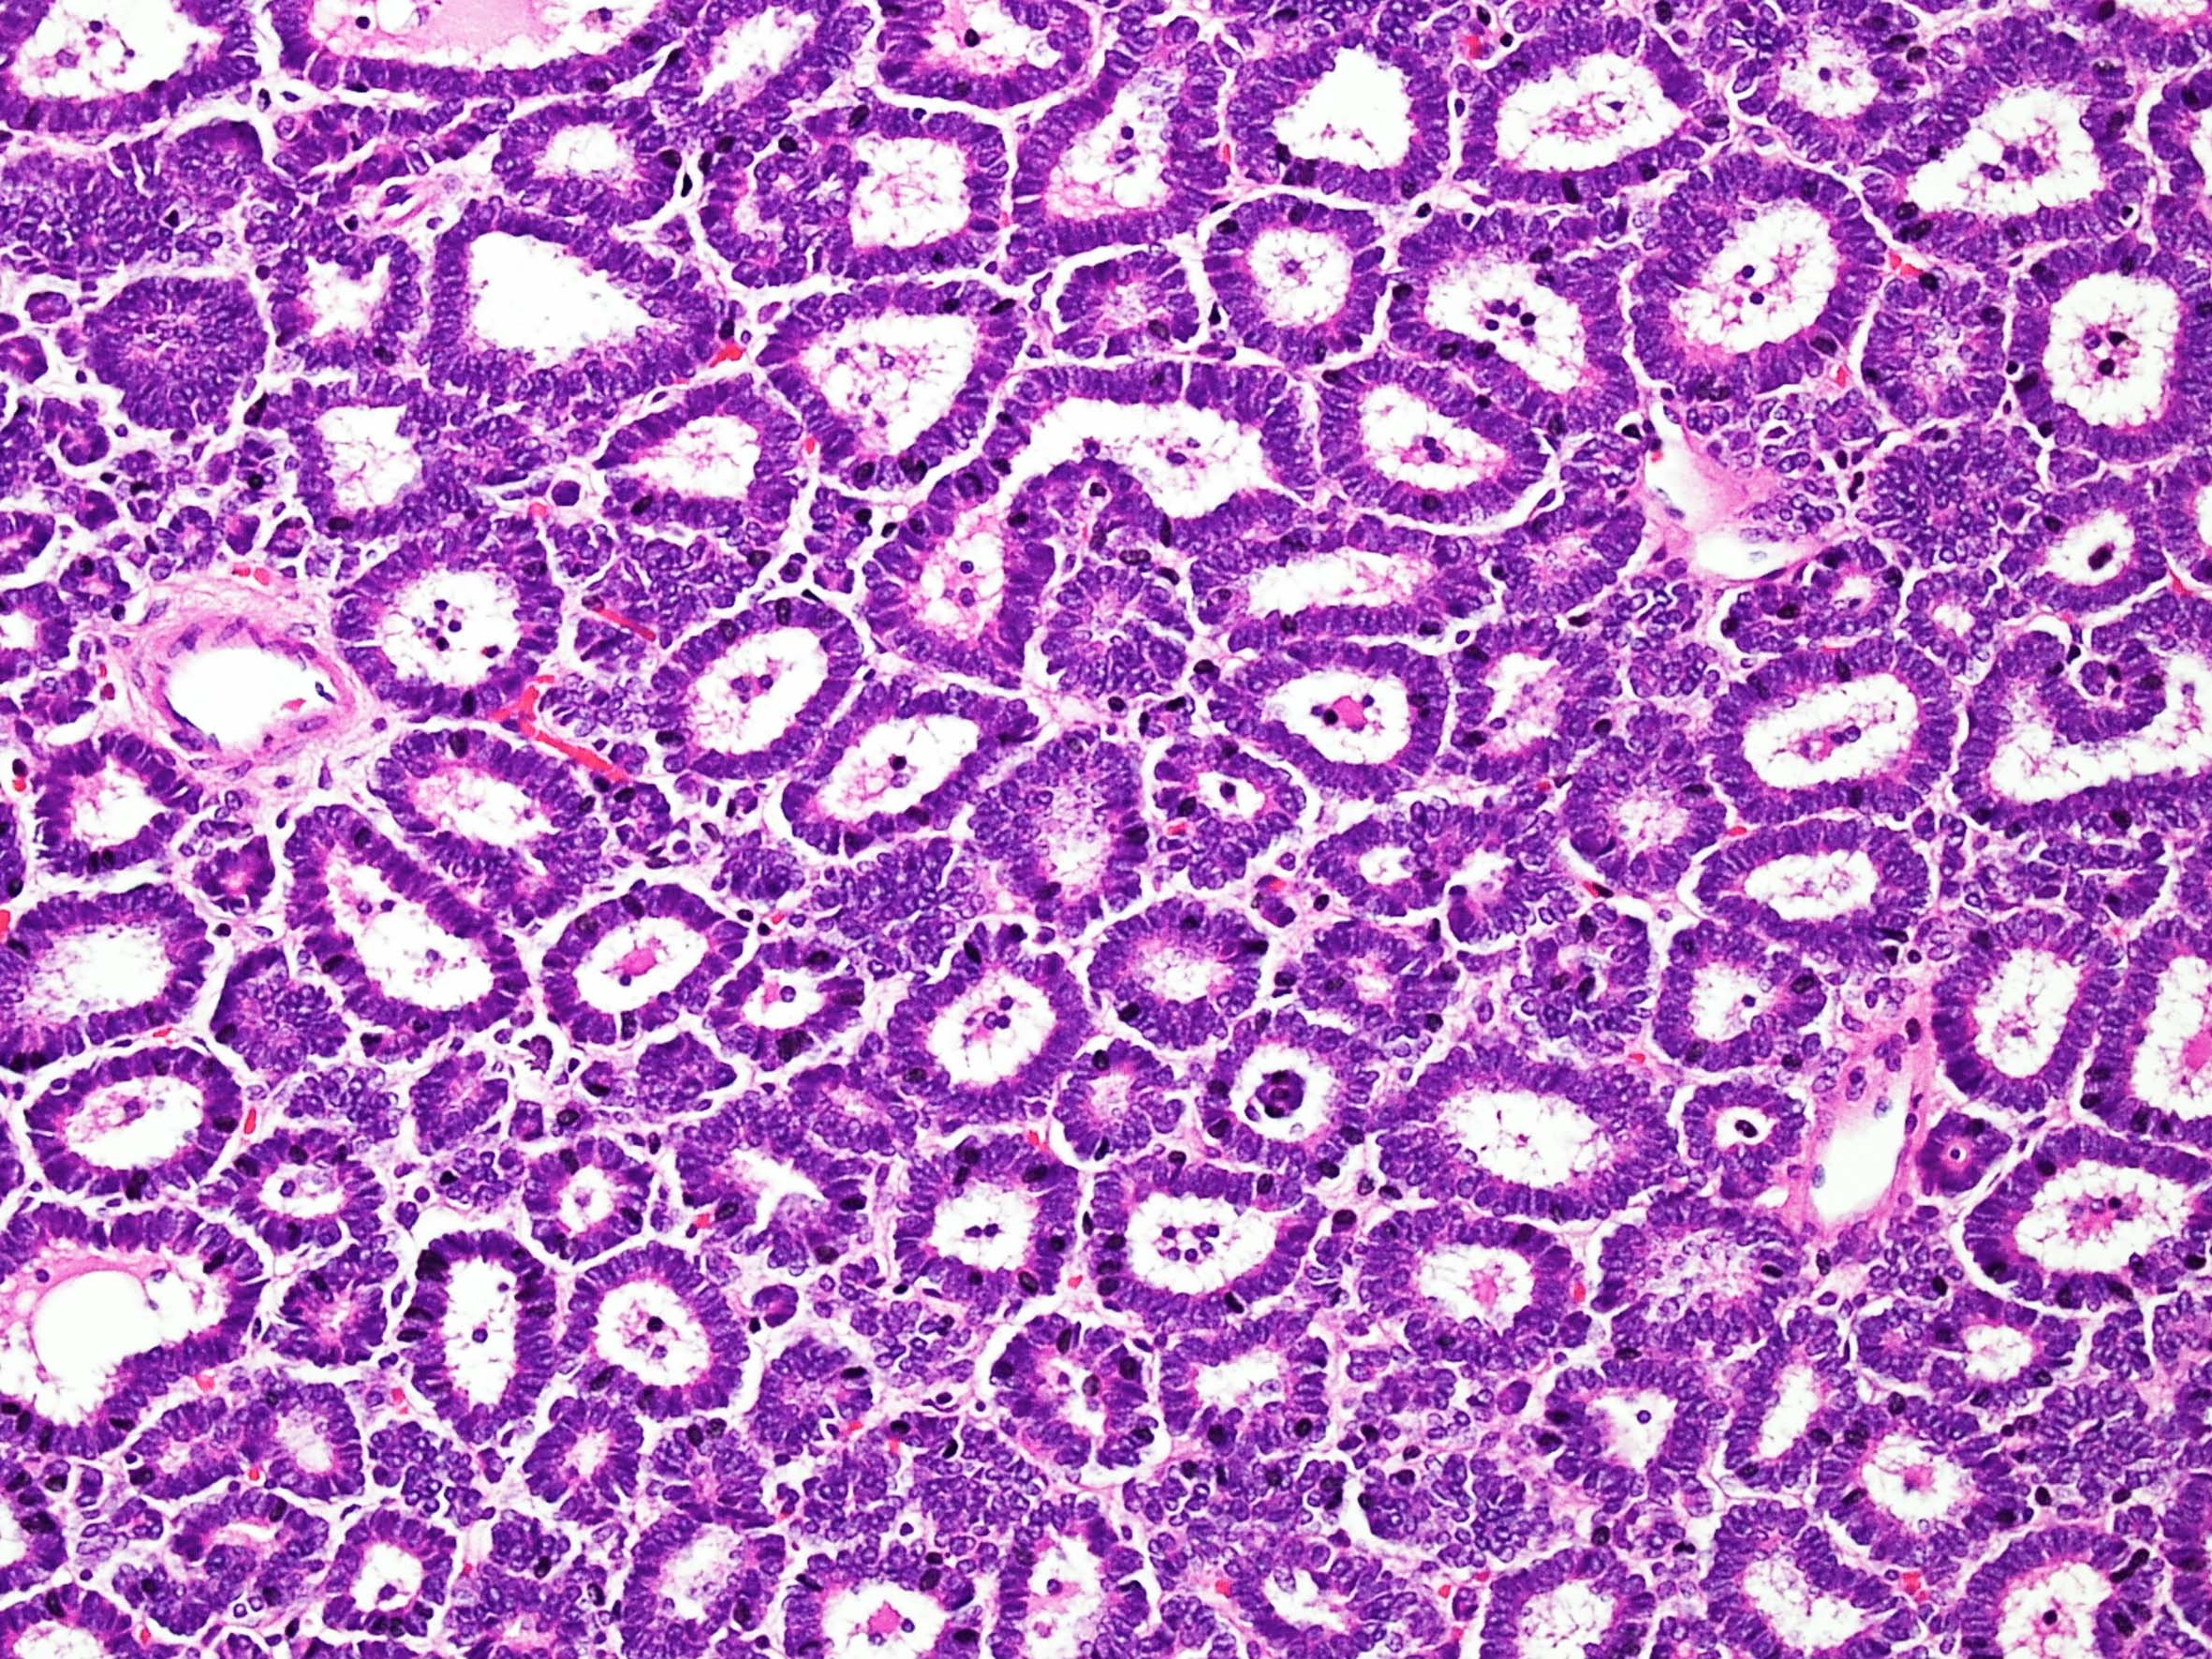

Metanephric adenoma